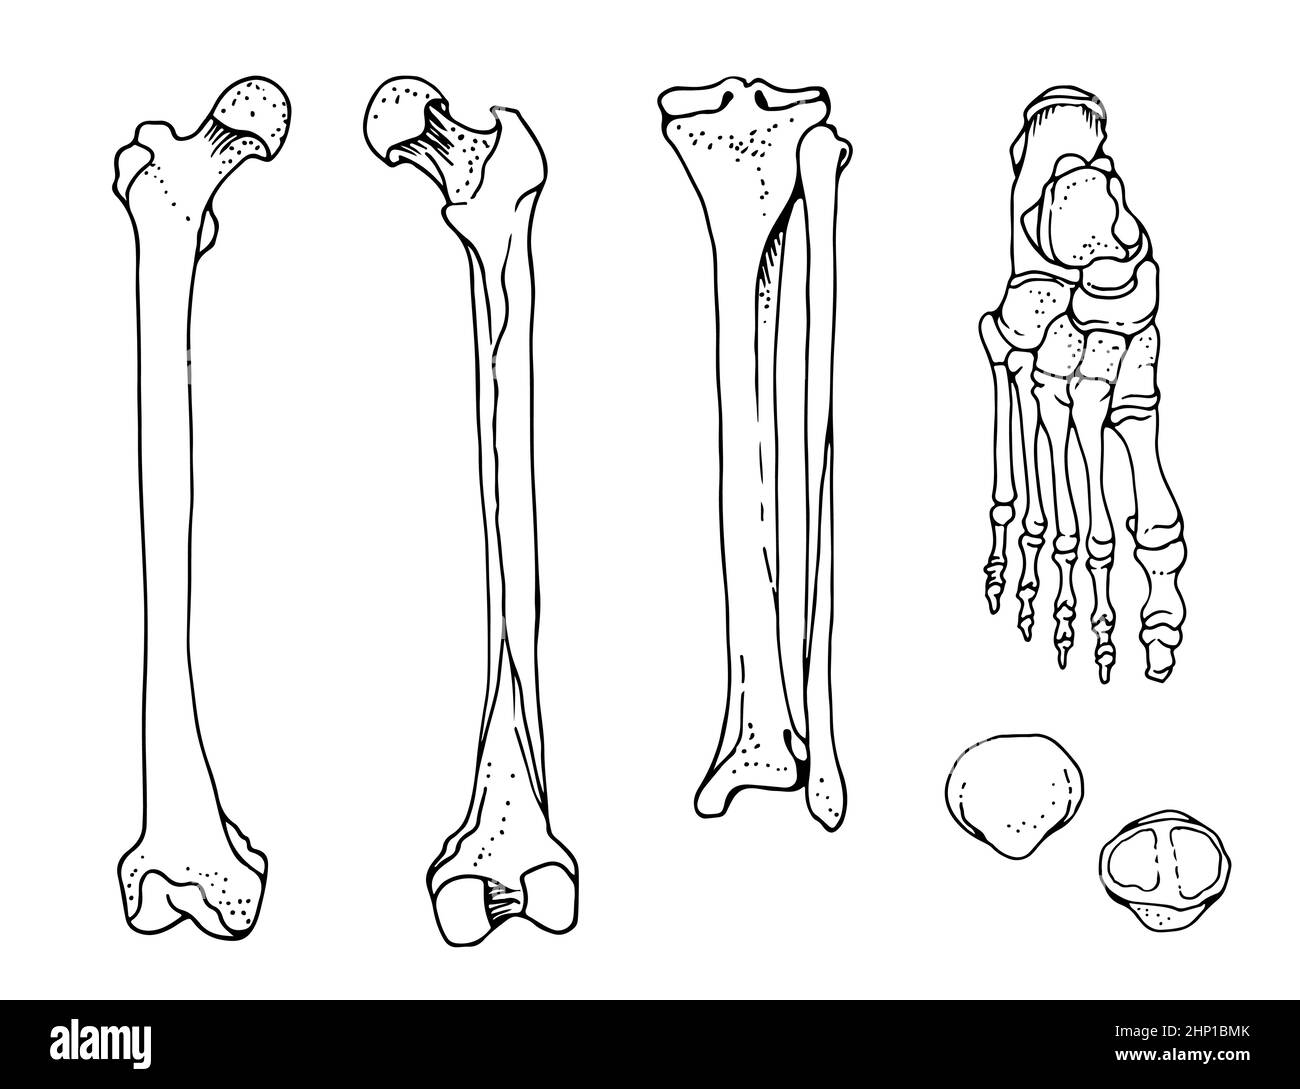

RF2HP1BMK–OS du pied humain, fémur, tibia et péroné, pied, rotule, illustration vectorielle dessinée à la main isolée sur fond blanc, ensemble anatomique orthopédique

RF2HP0BH3–Os humains tibia et péroné, illustration vectorielle dessinée à la main isolée sur fond blanc, esquisse anatomique en médecine orthopédique